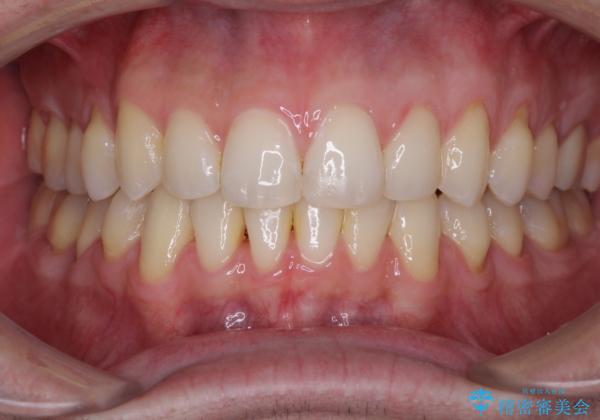

ディープバイトと叢生 インビザラインによる矯正治療

上顎奥歯の銀歯も気になっていたので、矯正治療の途中でセラミッククラウンへ変更し、その後歯列を仕上げていくこととしました。

ディープバイトもデコボコも改善され、気になっていた銀歯もセラミックとなり、患者様には大変満足していただきました。